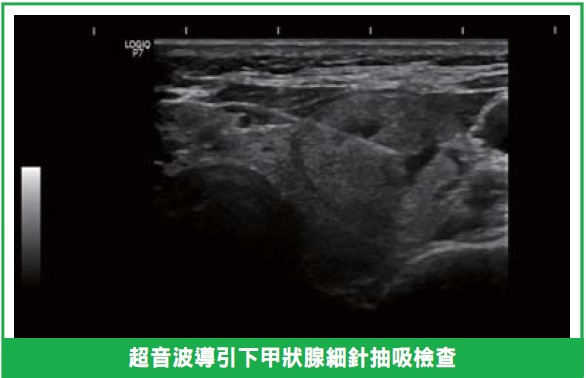

●超音波檢查:以探頭掃描脖子,檢查甲狀腺結節及頸部淋巴結。

●細針抽吸檢查:取少量細胞檢驗,疼痛輕微,類似抽血。